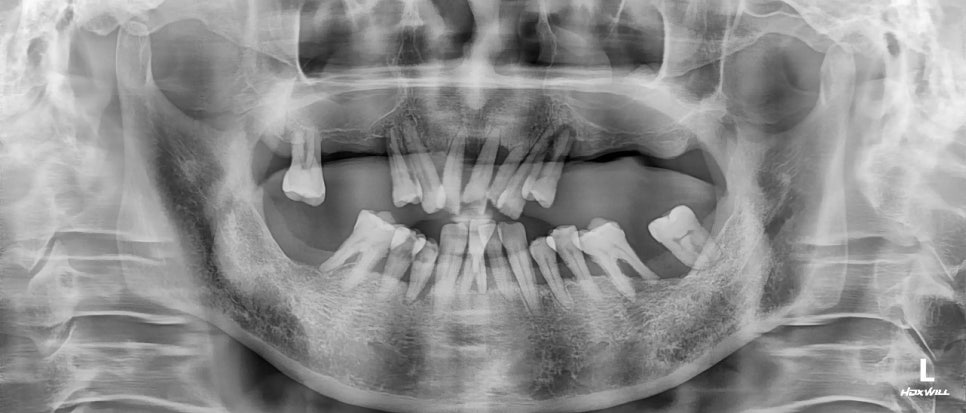

치아상실의 주요 원인은 약해진 잇몸?

‘잇몸이 약해서 임플란트를 못 한다고 하던데,

평생 틀니만 해야하는 건가요?’

임플란트가 필요해 내원해주시는 환자분들이

많이 물어보시는 질문입니다.

여기서 잇몸이 약하다는 것은 실제적인 잇몸이 아닌

잇몸 밑에 위치해있는, 치아를 지지하는

잇몸뼈(=치조골)를 의미합니다.

만약 자연치아를 지탱해주지 못할 만큼 이 잇몸뼈가

망가져 있다면 임플란트를 심기 어려울 수 있습니다.